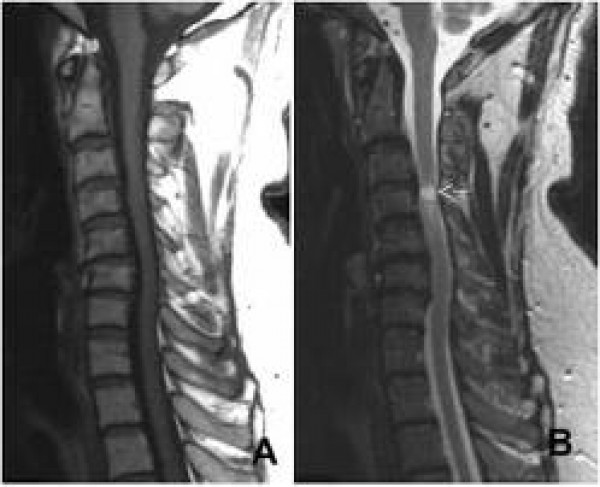

Ressonância magnética – avalia a estrutura da coluna em relação aos tecidos moles e também o grau de sofrimento medular

Tomografia – avalia a calcificação do disco, ligamentos, presença de osteófitos e avalia a hipertrofia das facetas articulares

Quando os sintomas estão evoluindo apesar do tratamento conservador, tendo diversos autores que ao compararem o tratamento cirúrgico com o conservador mostraram um melhor resultado nos pacientes que realizaram cirurgia. A cirurgia é realizada através de descompressões por via anterior ou posterior dependendo de cada caso.